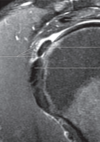

Q. De qué signo se trata y diagnóstico probable.

Signo del tallo de apio secundario a degeneración mucosa.